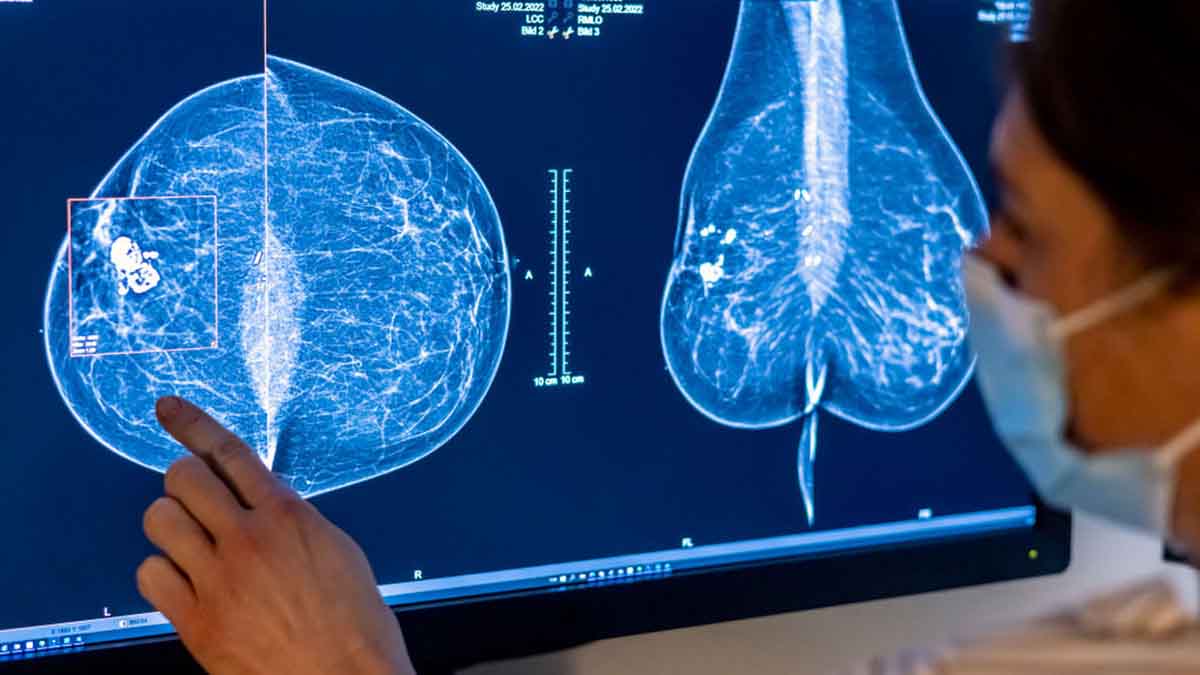

Aproximadamente la mitad de las mujeres mayores de 40 años tienen senos densos, con menos tejido graso y más tejido conectivo y glandular. Ese tejido aparece blanco en las radiografías, del mismo color que los crecimientos en el seno, lo que dificulta la lectura de las mamografías.

El tejido mamario denso es uno de los factores que pueden aumentar las posibilidades de que una mujer desarrolle cáncer.

Según las nuevas reglas, las mujeres con senos densos recibirán un memorando por escrito que les alertará que su estado “hace que sea más difícil detectar el cáncer de seno”.